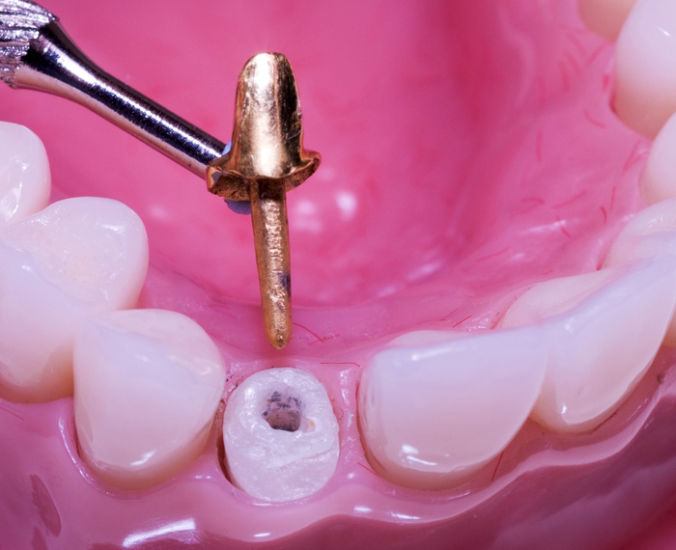

Remoção de Pinos

Remoção de pinos intrarradiculares e instrumentos fraturados (analisaremos cada caso).